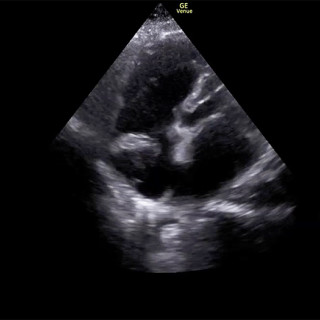

Kronisk transplantat-mot-vert-sykdom er en senkomplikasjon etter allogen stamcelletransplantasjon, og medfører kronisk inflammasjon og fibrose i forskjellige organer på grunn av feil regulering av donors immunceller. Sykdommen kan forekomme i alle organer, men sees hyppigst i hud, øyne, munnhule, gastrointestinaltraktus, genitalia, lunger, muskler, fascier og ledd. Kronisk transplantat-mot-vert-sykdom er assosiert med betydelig sykelighet og dødelighet, og behandling krever tett samarbeid mellom forskjellige deler av spesialisthelsetjenesten. Vi gir i denne artikkelen en klinisk oversikt over...